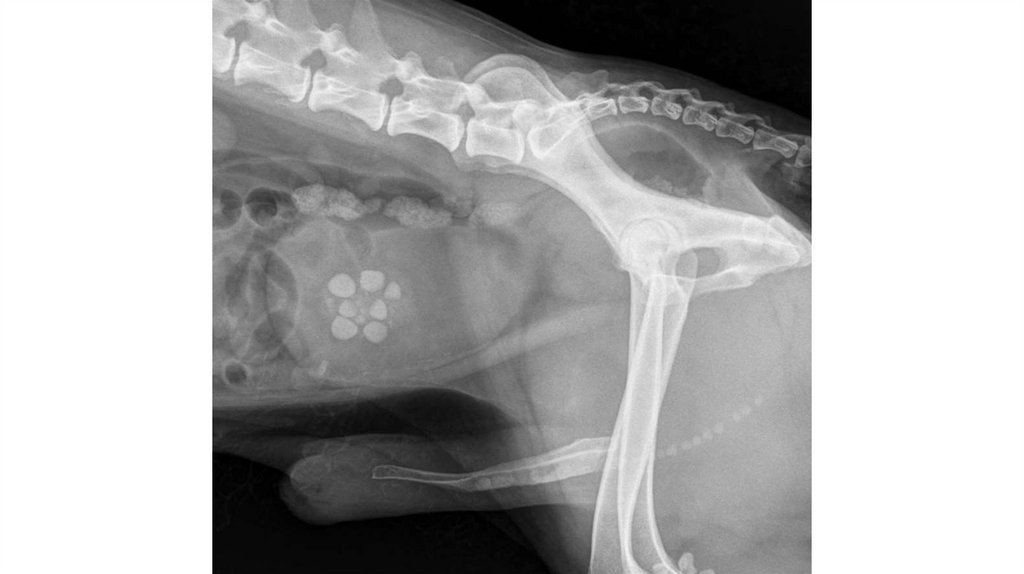

Врожденные патологии почек. Например у кошек встречается

врожденный поликистоз почек.